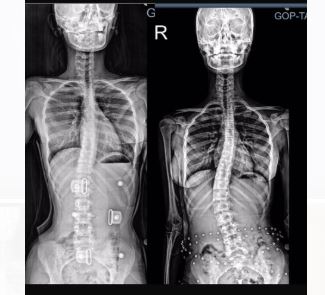

Günümüzde özellikle ergenlik döneminde artış gösteren omurga eğriliği, yani skolyoz, erken teşhis ve doğru tedaviyle kontrol altına alınabiliyor. Bursa’da protez ve ortez alanında yenilikçi yaklaşımlarıyla öne çıkan Ortopro Ortopedi, skolyoz tedavisinde modern ve kişiye özel korse uygulamalarıyla fark yaratıyor.

Skolyoz, omurganın yana doğru eğilmesiyle oluşan bir iskelet sistemi bozukluğudur. Çoğunlukla çocukluk veya ergenlik döneminde ortaya çıkar. Eğriliğin ilerlemesini durdurmak ve omurgayı desteklemek için erken müdahale büyük önem taşır.

Ortopro Ortopedi, skolyoz hastalarına yönelik olarak kişiye özel 3D modelleme ve ölçümleme teknolojileri ile hazırlanan modern skolyoz korseleri üretmektedir. Gelişmiş analiz cihazlarımız ve uzman teknik kadromuz sayesinde, her hastanın omurga yapısına özel olarak tasarlanan korseler, tedavi sürecinin başarısını artırmaktadır.